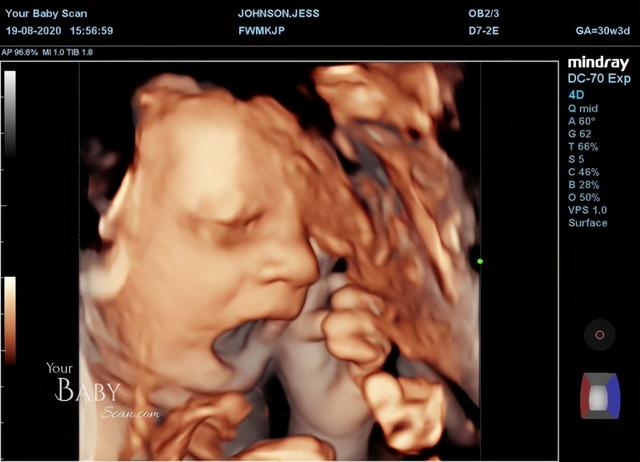

近日,據《地鐵報》報道,由於新冠肺炎疫情,英國一名24歲懷孕38周的孕媽媽傑西·約翰遜為了想提早見到自己的孩子,和23歲的丈夫大衛·劉易斯去了私人診所進行4D超音波掃描。

孕媽媽傑西說:「我們進去後,醫生就開始進行掃描。孩子看起來似乎有點害羞,還遮住了臉,打了幾個呵欠,好像在說他現在累了。掃描快結束的時候,他又開始把自己的臉遮住了,好像在說,『你已經拍夠了,現在離我遠點』。」

與此同時,這對夫婦還意外看到他們的兒子在掃描中對鏡頭豎起中指的手勢,「在掃描結束前5分鐘,他還對我們豎中指,好像在說,『爸爸媽媽,夠了,現在別管我了。』我的另一半看到了,但並沒有馬上意識到發生了什麼。我問超聲師,他剛才是不是把手指豎起來了?她說,『我想是的』。說實話,我們都很震驚。他把它舉起來,然後又放下來,好像在說,『我不是故意的』。他似乎知道這樣做很淘氣,但他還是那樣做了,」

而準爸爸大衛也表示:「等到他出生,我一定會嘲笑他。我已經把掃描照片給朋友、家人和所有周圍的人都看了。很多人都表示,這張掃描圖太棒了。」